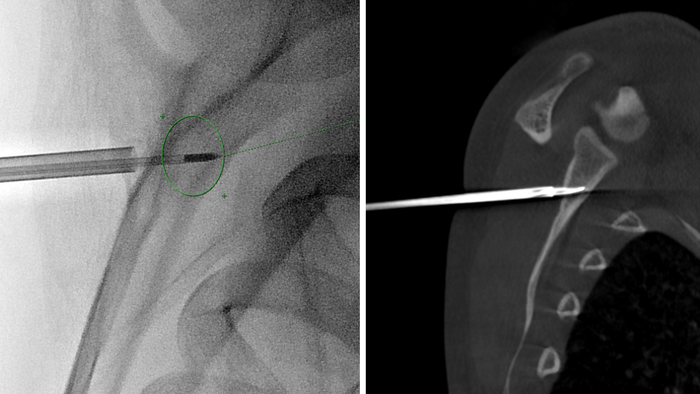

"Ekip sử dụng kim chuyên dụng để định vị chính xác tổn thương, sau đó dùng năng lượng sóng cao tần để triệt tiêu hoàn toàn khối u trong xương. Phương pháp này giúp loại bỏ tổn thương mà không cần mổ hở, giảm tối đa đau đớn và rút ngắn thời gian hồi phục" – TS.BS Cương cho biết.

Đốt sóng cao tần triệt tiêu khối u dưới hướng dẫn của hệ thống DSA